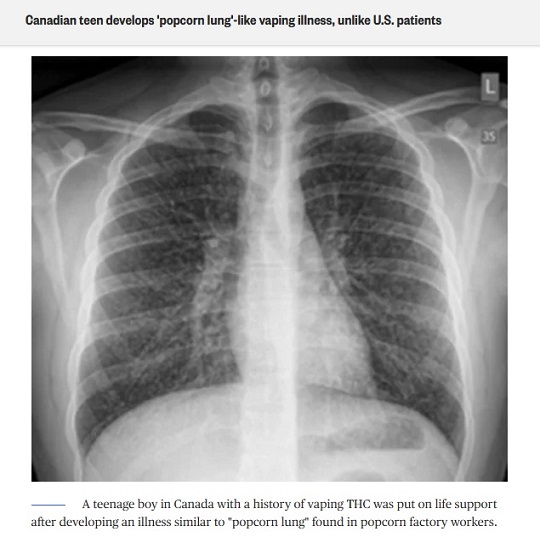

โรคหลอดลมฝอยอักเสบอุดกั้น เป็นที่รู้จักทั่วไปในชื่อ โรคปอดป๊อปคอร์น เนื่องจากพบการระบาดอย่างแพร่หลายในกลุ่มผู้ป่วยที่ทำงานในโรงงานอบข้าวโพดคั่วในช่วงต้นยุค 2000s

แม้สารไดอะเซทิลจะไม่เป็นอันตรายสำหรับการบริโภค แต่ส่งผลเสียต่อระบบทางเดินหายใจหากสูดดมเป็นเวลานาน เพราะการสะสมสารไดอะเซทิลทำให้เกิดการอักเสบที่ผนังหลอดเลือดในปอด เกิดเนื้อเยื่อแผลเป็นที่ผนังหลอดเลือด ทำให้หลอดเลือดแคบลง นำไปสู่โรคหลอดลมฝอยอักเสบอุดกั้น

นักวิจัยของมหาวิทยาลัยฮาร์เวิร์ดนำตัวอย่างบุหรี่ไฟฟ้า 51 ยี่ห้อมาทำการตรวจสอบ พบว่ามีถึง 39 ยี่ห้อหรือเกือบ 80% ที่มีสารไดอะเซทิลเป็นส่วนประกอบในน้ำยา

ผู้สูบบุหรี่ไฟฟ้าที่ได้รับสารไดอะเซทิลเป็นเวลานาน เพิ่มความเสี่ยงการป่วยเป็นโรคปอดป๊อปคอร์น อาการที่สังเกตได้คือ อาการไอ หายใจลำบาก หายใจมีเสียงหวีด รู้สึกเหนื่อยง่าย และมีอาการไข้